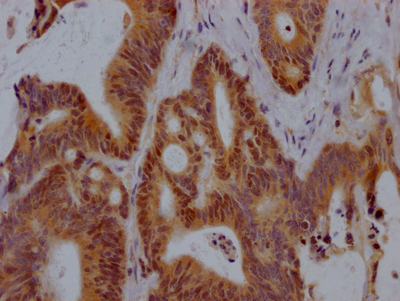

圖片:

應用范圍:IHC,ELISA

Application Recommended Dilution IHC IHC-p:1:50-300 ELISA 1:10000-20000 -